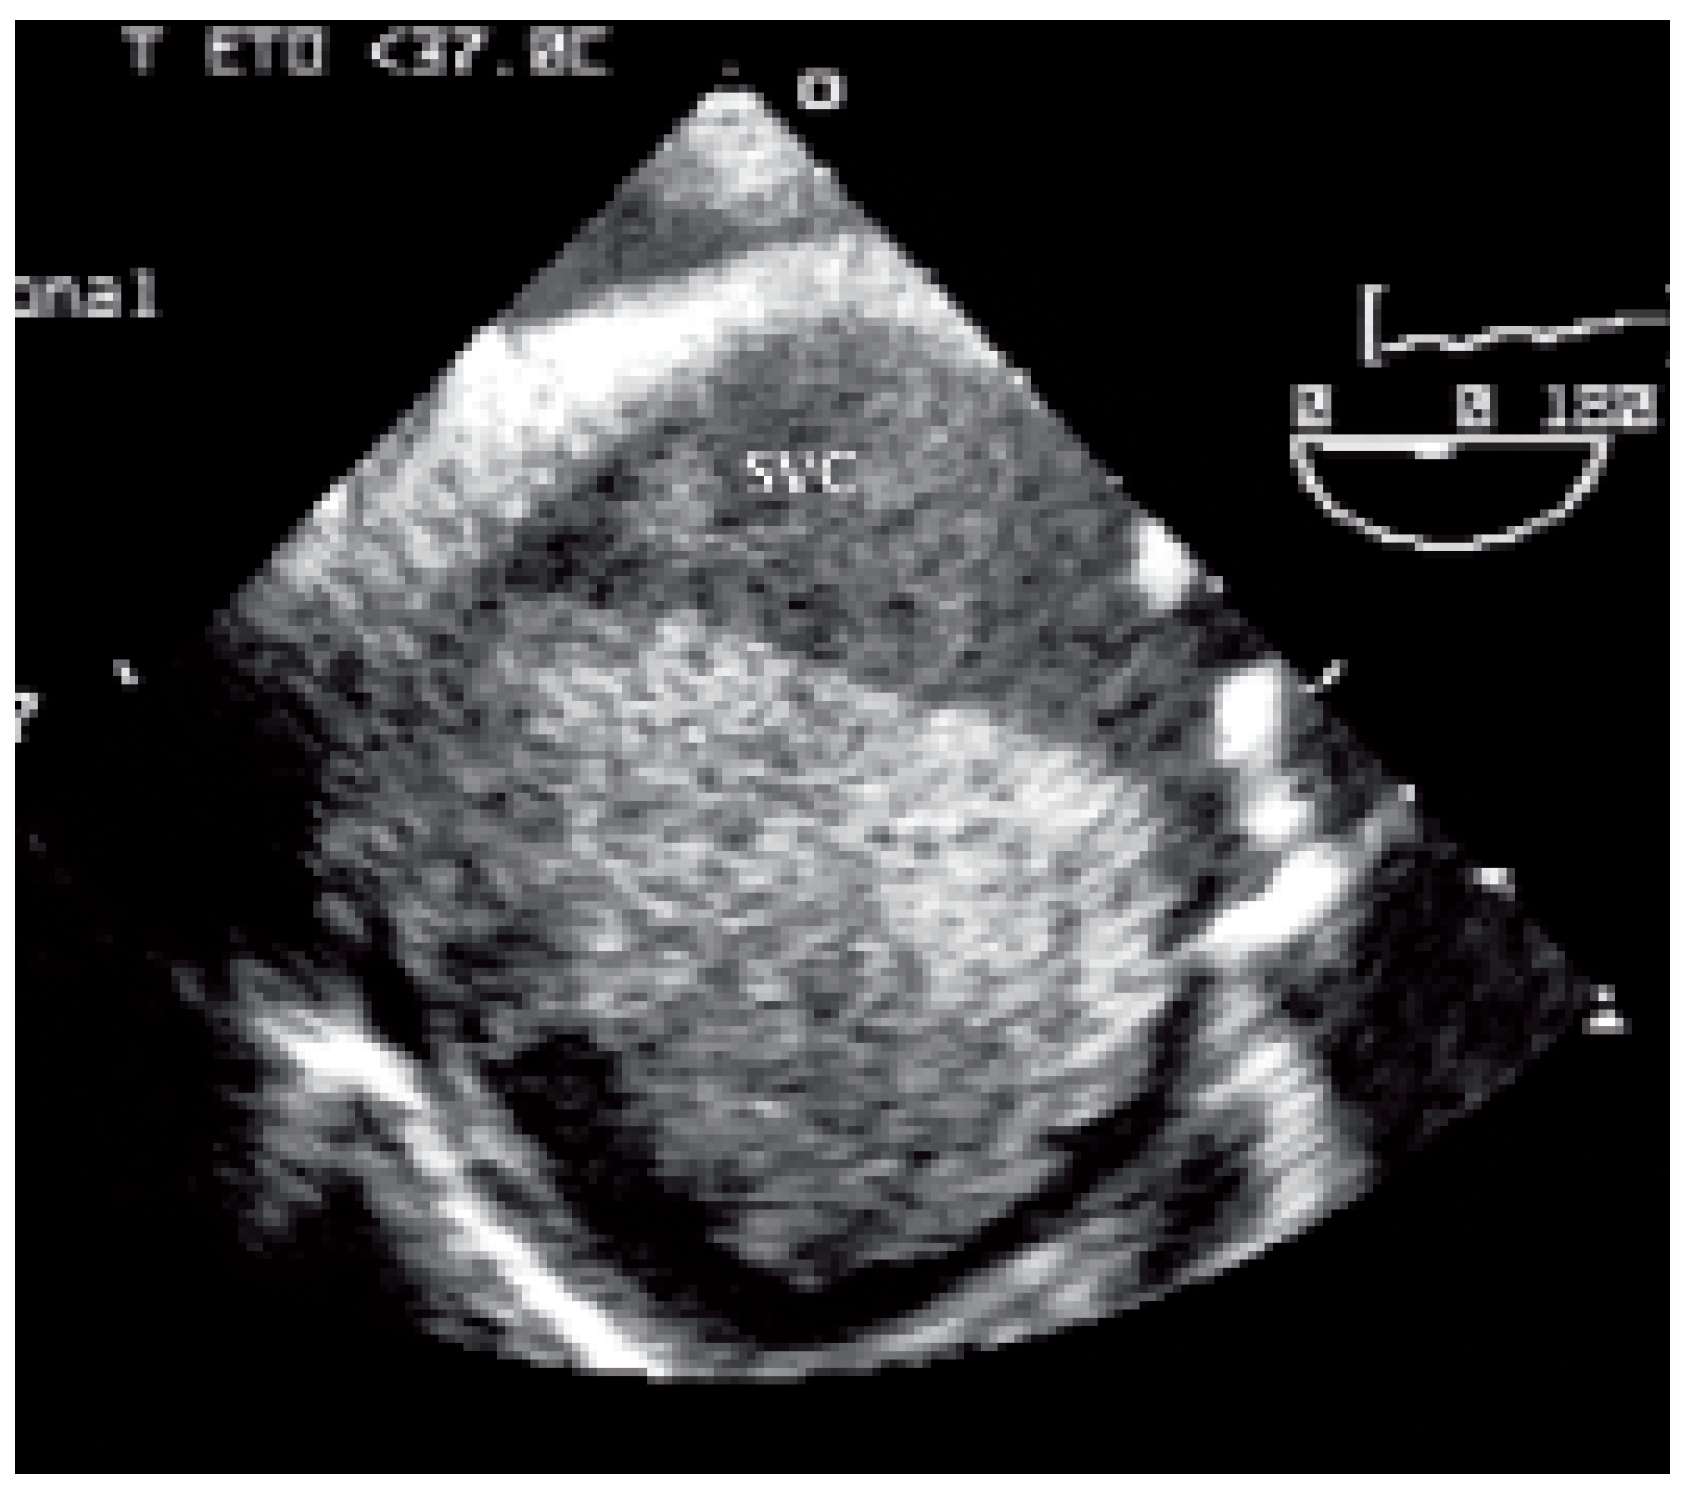

Case report